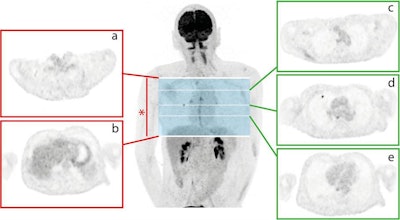

This illustration shows the annotation of PET images for training and testing of the deep-learning algorithm. The researchers assigned the upper (a) and lower (b) lung limits for each subject, with only slices within this lung volume (*) utilized for further analysis. Every image was annotated on a slice-by-slice basis as 0 if no nodule was present (e.g., slices c and e) or 1 if an FDG-avid nodule was present (e.g., slice d). Image courtesy of European Radiology and Schwyzer et al.BSREM vs. OSEM